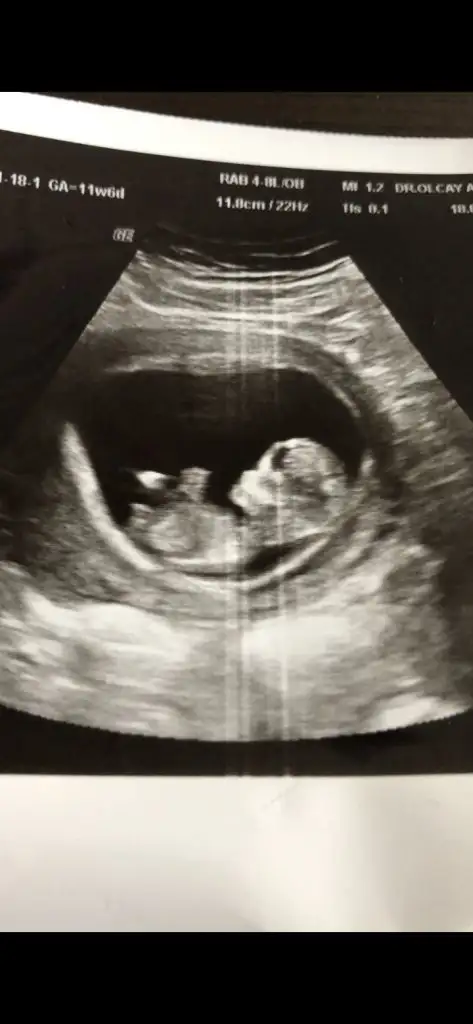

Erkek görünüyorMerhaba 11+6 tahmin edermisiniz

Net değil nubu emin olamadim başka USG varsa paylaşın sanki kız ama emin değilimMerhaba 12 haftalık tahmin edebilir misiniz